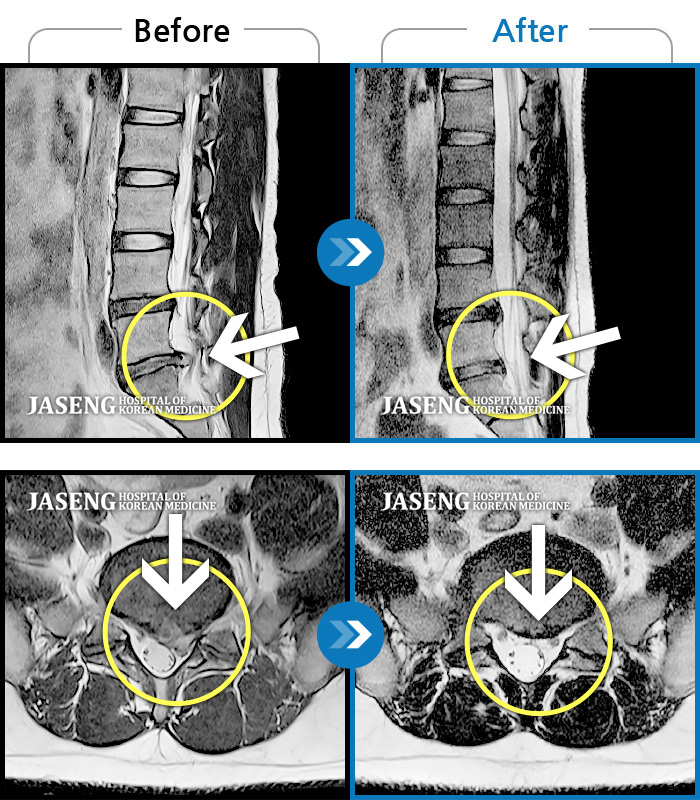

허리디스크

인천 · 조남훈 원장

허리가 너무 아프고 다리가 저려요.

촬영시기

2018.04.23 ~ 2025.12.05

2025.12.19